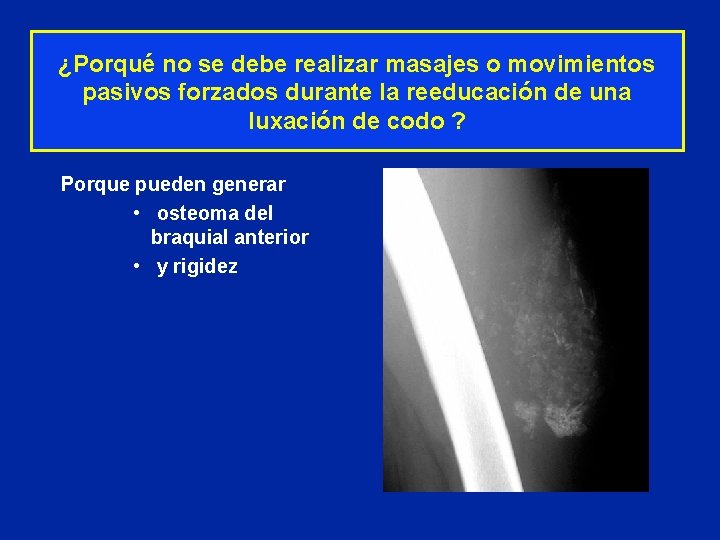

¿Porqué no se debe realizar masajes o movimientos pasivos forzados durante la reeducación de una luxación de codo ?

¿Porqué no se debe realizar masajes o movimientos pasivos forzados durante la reeducación de una luxación de codo ? Porque pueden generar • osteoma del braquial anterior • y rigidez